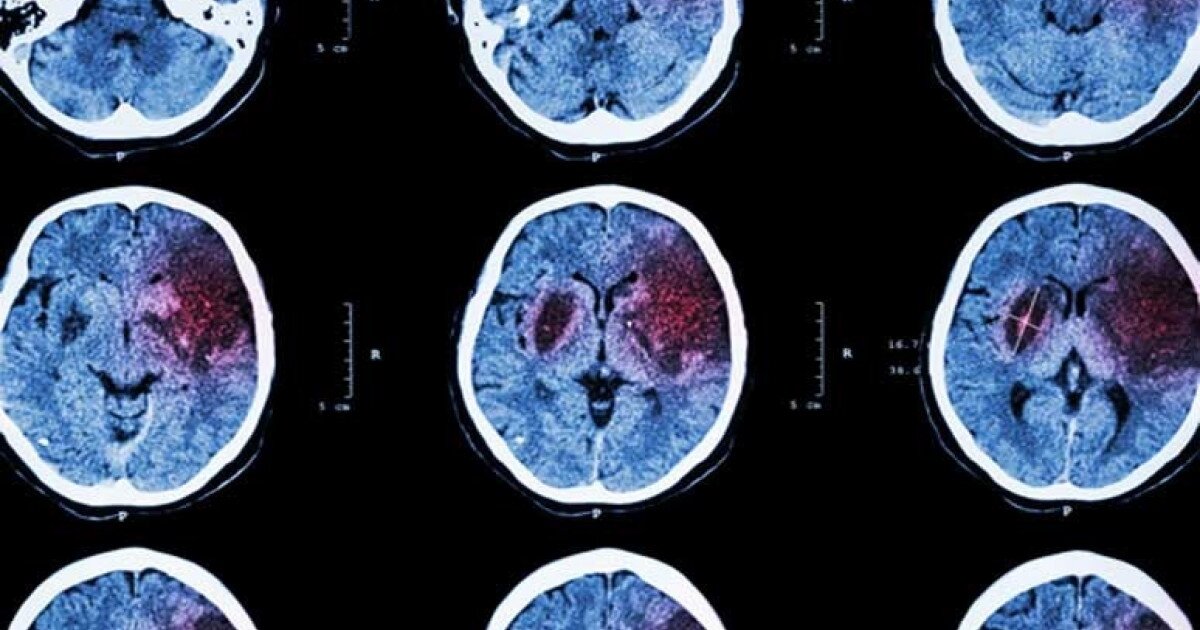

Los accidentes cerebrovasculares se afianzan como uno de los mayores desafíos para la salud pública a nivel global. Las proyecciones oficiales anticipan un incremento sostenido de casos en los próximos años, con repercusiones tanto para los sistemas de salud como para la población en edad laboral.

La presión arterial elevada está implicada en aproximadamente la mitad de los accidentes cerebrovasculares, tanto hemorrágicos como isquémicos. La hipertensión aumenta la presión sobre las arterias, especialmente en el cerebro, lo que puede provocar hemorragias. Además, el daño en el flujo sanguíneo favorece la formación de coágulos que pueden obstruir arterias cerebrales y desencadenar un evento isquémico.